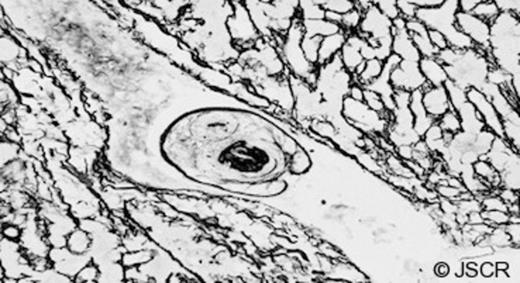

Over the next 48 hours vasopressors were weaned and he was extubated. One further short episode of wheeze was effectively managed and he was transferred to the ward. Biopsies showed irregular liver architecture with fibrosis indicating a chronic process (Figure 3). Higher magnification identified a parasite (a hydatid protoscolex) within a hepatic venule (Figures 4&5) and a diagnosis of hydatid disease (Echinococcus granulosus) was made. He was treated with albendazole 400mg bd and discharged home on day 16.

Higher magnification H&E stained image showing a hepatic venule containing a characteristic echinococcal protoscolex with hooklets visible in section.

This is a rare case of anaphylaxis to cystic hydatid disease initiated by leakage into the vasculature following trauma. Cases of anaphylactic shock have been reported as the only manifestation of hydatid disease in cases of rupture into the peritoneal cavity and is considered in endemic regions (1,2,8). Buyuk et al (9) reported a case where hydatid disease led to death with cyst content spreading into the bloodstream. Peritoneal rupture of the cyst did not occur in our case but the hydatid protoscolex found within a hepatic venule (Figures 4&5) indicates that the patient had intravascular exposure to the parasite. Intra portal venous rupture and probable manipulation led to anaphylaxis.